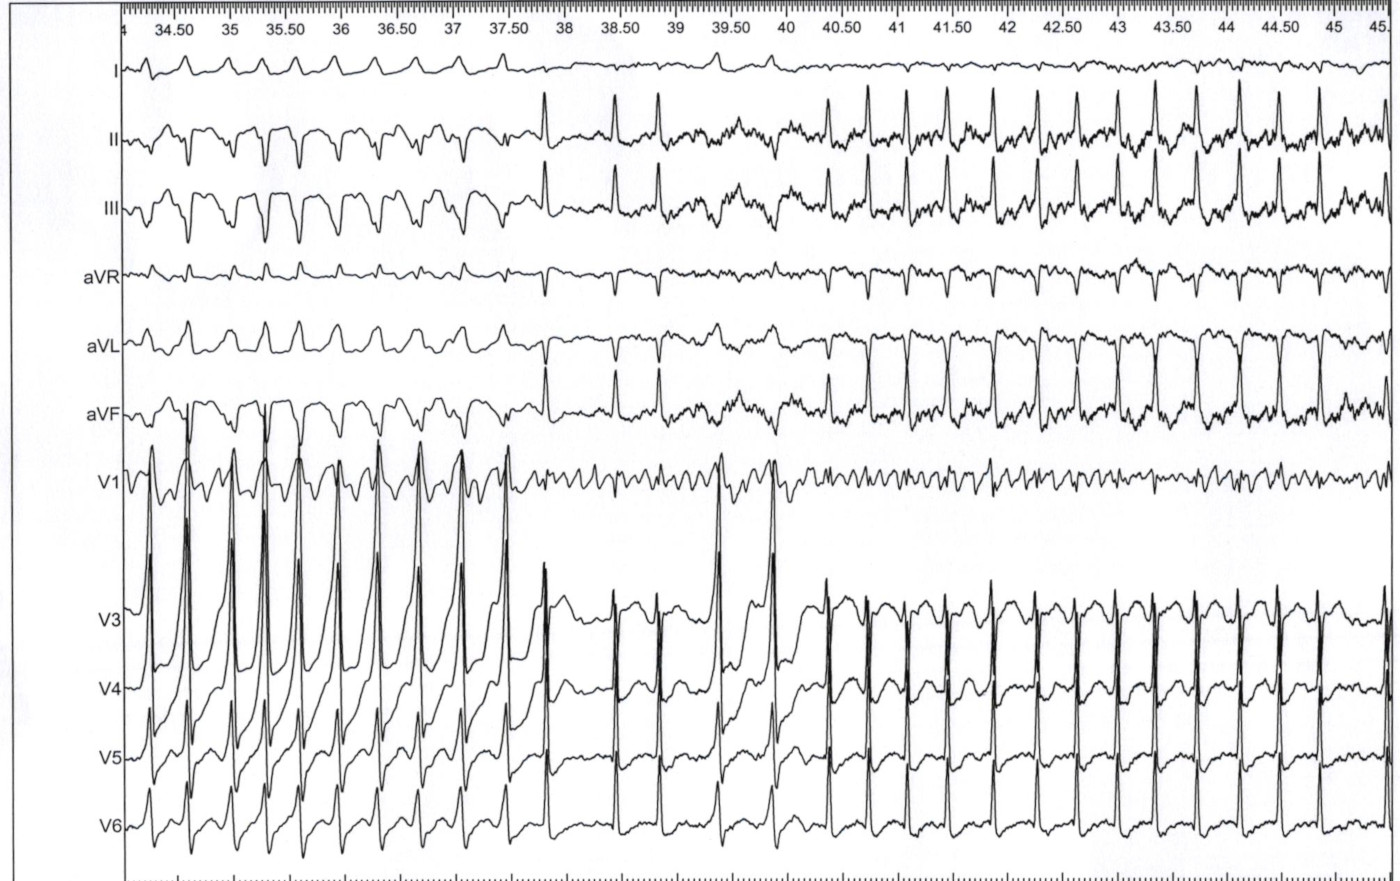

Preexcited AF - note leads II and V6

ecg_af.jpg

Venogram

diverticulum.jpg

Ablation at ventricular insertion

ventricular_insertion_abl.jpg

Successful location at neck with CSE potential

succ_site.jpg